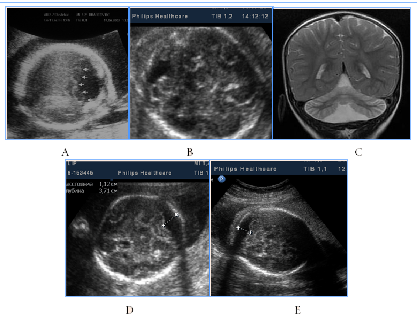

All cases with prosencephalic malformations had an adverse catamnesis connected with combined pathology. Two cases of alobar holoprosencephaly (HPE) and syndromic semilobar HPE were connected with perinatal losses. Syndromic lobar HPE with partial callosal agenesis and septo-optic dysplasia didn't have perinatal consequences, but the clinical outcome for the child was unfavorable as well (Figure1). HPE in 3rd trimester, 4 cases:

Figure 1 HPE in 3rd trimester, 4cases.

А) Alobar syndromic HPE with the residual mantle of the cortex at the base of the brain, severe progressive disgenetic hydrocephalus with macrocrania, intranatal death, clinical intranatal mismatch of head and pelvic size, fetus-damaging operation.

B) Isolated alobar HPE, cup-shaped type, the biggest part of the cortical mantleis attended, but it does not cover a single ​​anterior ventricular area, infant death.

C, D, E). Semilobar syndromic HPE with callosal agenesis. The ventricles are connecting through a narrow channel across the midline, thalamuses partially fused, IUGR, absent umbilical end-diastolic flow, antenatal death.

F). Fetal NSG and MRI of the newborn with syndromic lobar HPE, partial callosal agenesis, septo-optic dysplasia, US variant with merged, widely separated narrow acute-angled anterior horns of ventricular and dilated Verga’s cavity, long-term neurological disorders, severe visual impairment, epilepsy in the kid.